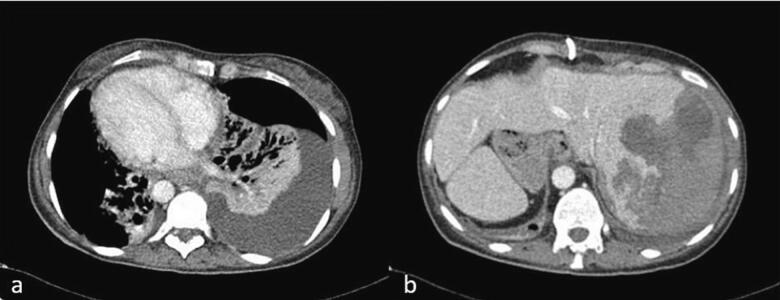

A 41-year-old female patient, known to have Kartagener syndrome (SIT, chronic sinusitis, and bronchiectasis) [ref. 6], as well as asthma (on Advair 250/50), and a history of two C-sections (in 2003 and 2005), presented to the emergency department with left upper quadrant abdominal pain associated with fever, nausea, and vomiting. An ultrasound revealed acute cholecystitis, and the patient was taken to the operating room for laparoscopic cholecystectomy, performed by a practicing general surgeon. In the operating room, after gaining access to the abdomen, it was discovered that the patient had a severely inflamed gallbladder with a thickened wall (Fig. 1a). The surgeon attempted to provide a mirror image approach in the trocar position but was unsuccessful due to his hand position and function, as shown in the video of the operation (please see the video). The surgeon’s hands were crossed, with the right-hand dissecting and the left retracting (Fig. 1b). The gallbladder was successfully dissected from the liver bed, and the surgery was completed. The patient was discharged home on post-operative day one after the removal of the abdominal drain, which contained serous non-biliary output.

Her hospital course was complicated with pneumonia on top of her pre-existing bronchiectasis (Fig. 4a) and a large subcapsular hematoma of the liver resulting from the PTC procedure (Fig. 4b), requiring multiple blood transfusions and IV antibiotics for the pneumonia. Four weeks later, her PTC stents were upsized from 10 Fr to 12 Fr. A follow-up CT scan revealed a resolution of the subcapsular hematoma, and the decision was made to proceed with a hepaticojejunostomy six weeks after her initial operation.